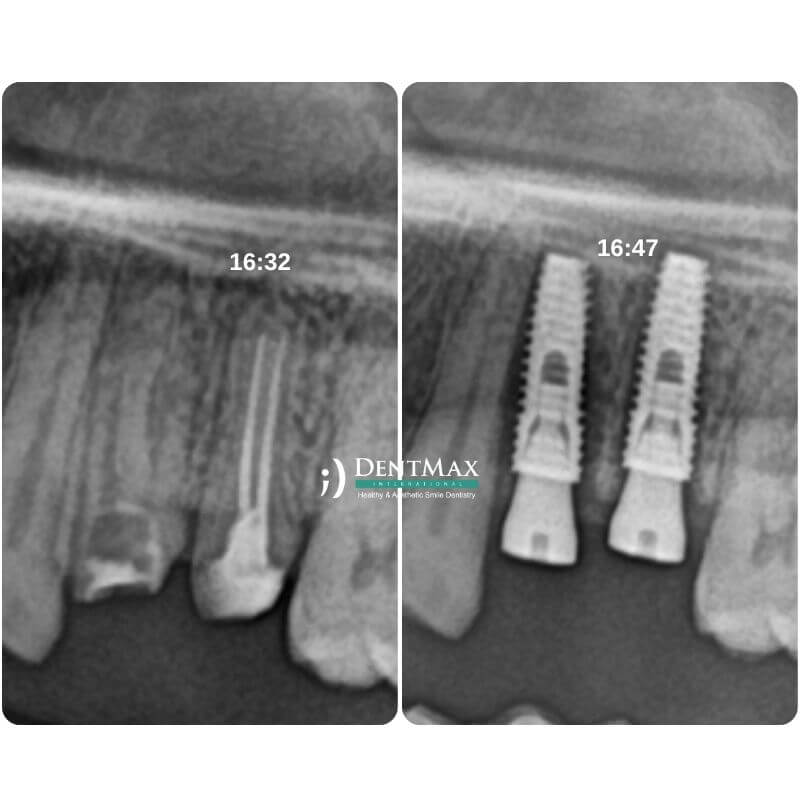

كم من الوقت يجب أن تنتظر لزرع الأسنان بعد خلع السن؟